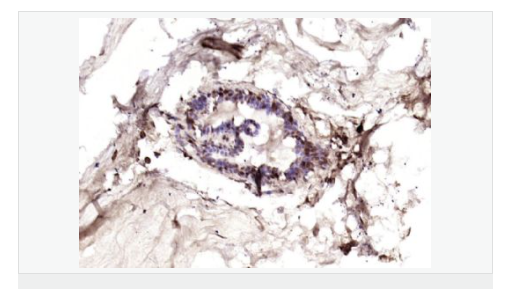

產(chǎn)品應用ELISA=1:5000-10000 IHC-P=1:100-500 IHC-F=1:100-500 IF=1:100-500 (石蠟切片需做抗原修復)

細胞膜受體(Membrane Receptors) c-erbB-4蛋白過去一直為乳腺癌基因研究的主要方向,研究乳腺癌組織學分級及術(shù)后生存期的關(guān)系。目前認為他與細胞增殖活性和激素受體有一定的關(guān)聯(lián),有學者將c-erbB-4蛋白研究用于神經(jīng)內(nèi)分泌蛋白為主。